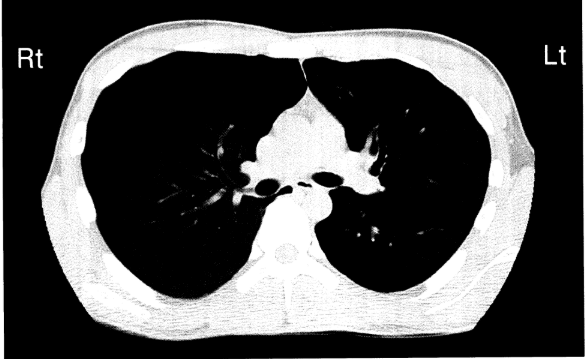

A さん(27歳 男性) は、 突然の胸痛と呼吸困難があり、 救急外来を受診した。意識は清明。身長179cm、体重63kg、 胸郭は扁平である。 20歳から1日50本の喫煙をしている。 バイタルサインは、 体温36.1°C、 呼吸数22/分、 経皮的動脈血酸素飽和度 (SpO2) 96% (room air) である。胸部CTを以下に示す。

◆胸部CT画像の評価

・画像を見ると、右側(Rt)において肺の虚脱を示唆する所見が認められる。

・右肺の虚脱(無気肺)または気胸が疑われる。

・特に、若年・痩せ型・喫煙歴があることから、自然気胸の可能性が高い。

3. 解答:右肺野の呼吸音は減弱している(→正解)気胸がある場合、気体が胸腔内に貯留し、肺が虚脱するため、患側の呼吸音は減弱する。画像所見と臨床症状からも、右肺の虚脱が示唆される。

4. 解答:左胸腔内は液体成分で占められている。(→不正解)胸水貯留(液体成分)の所見はない。画像では、左側(Lt)に特に液体の貯留を示唆する白い陰影は認められない。